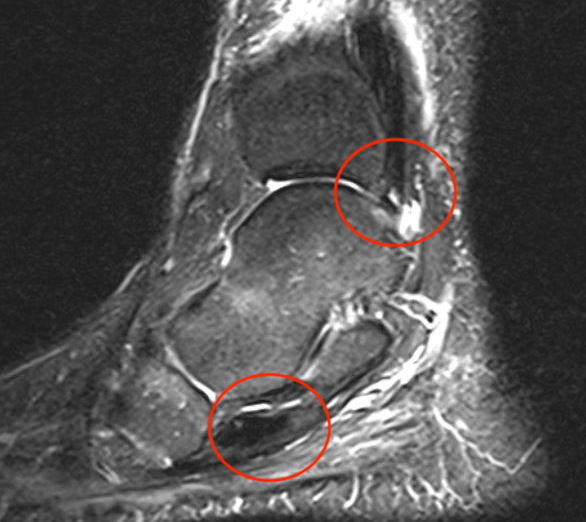

MRI

Tendonitis - fluid around tendon

Tendinopathy - tendon thickening

Tears

Tear tibialis posterior with 10 cm gap